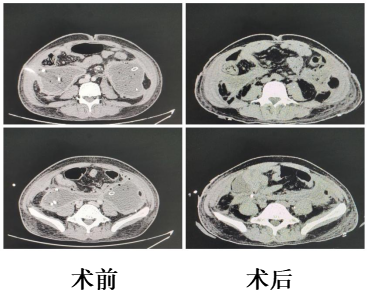

近日,我院急诊外科通过微创腹膜后小切口,成功为一名重症胰腺炎合并胰腺坏死组织感染、腹膜后脓肿的患者实施手术,为患者解除病痛,开启康复新篇章。 患者是一位 37 岁的男性,曾因重症胰腺炎在重症监护...